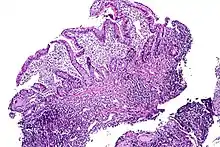

Tissue of the ileum with inflammatory changes due to Crohn's disease

Crohn's disease – also known as regional enteritis, it can occur along any surface of the gastrointestinal tract. The most common location for Crohn's disease to manifest, with or without the involvement of the colon or other parts of the GI tract, is in the terminal ileum (the final segment of the small intestine).[5] In 40% of cases, it is limited to the small intestine.[6]